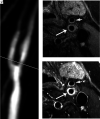

FIG 4.

Representative images of recurrent plaque. TOF-MRA (A) shows high-grade restenosis of the carotid bulb. The white line indicates the location of VWMRIs. Pre- (B, left image) and corresponding postcontrast (B, right image) VWMRIs show enhancing eccentric wall thickening with ulceration (asterisks), suggestive of a recurrent plaque. The corresponding specimen sections stained with MOVAT (C) confirm the diagnosis of recurrent plaque. The asterisk indicates ulceration. The arrowheads in B and C indicate the lumen. VWMRIs were acquired using an electrocardiogram-gated double inversion recovery turbo spin-echo sequence (TR/TE/echo-train, 1 RR/9 ms/10; resolution, 0.35 × 0.35 × 2 mm3).